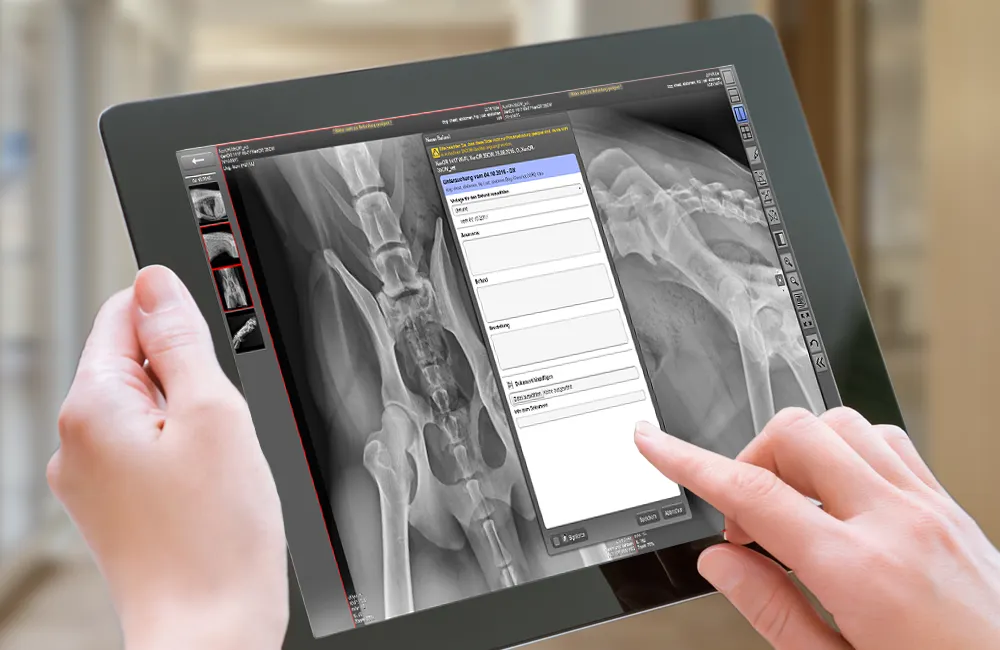

View X-ray solutiondicomPACS®MobileView is a web-based system that enables location-independent viewing and editing of radiological image data on mobile devices

dicomPACS®MobileView is a web-based system that enables location-independent viewing and editing of radiological image data on mobile devices